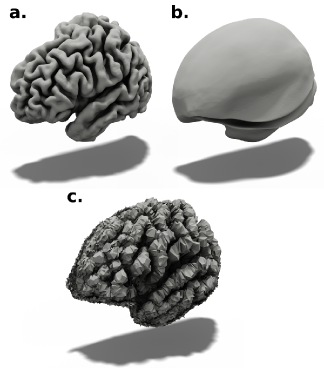

The reconstruction of regular surfaces from a deformable model is a subtle trade off between finding the right parameterization or a suitable level of regularization during training. The delicacy of this problem is illustrated in Figure 1. First, one can employ multiple penalty functions as Chamfer normal, normal consistency, Laplacian loss, or edge length loss [75, 77]. It is worth mentioning that without such penalizations, a deformable model will learn non-smooth deformations, which leads to irregular meshes (as shown in Figure 1.c). However, those penalizations simply encourage the reconstructed surface to be regular. The second approach consists of parameterizing the set of learned deformations; this approach is favored in our paper since it allows stronger theoretical guarantees and is not subject to hyper-parameter tuning. A natural framework to generate invertible deformations is to consider a flow ODE [20, 73]. This framework has been successfully applied in pattern recognition and image registration [19, 7, 2, 3]. The main idea is to consider the mapping as the solution at time of an initial value problem (IVP) of the form,

In [52, 30], the problem is solved using a black-box neural ODE [9] and by learning a neural vector field . Despite allowing learning a time-dependent vector field, this approach has shown its limitations in our targeted application. Cortical surfaces are unique to each individual; indeed, the cortical folding patterns are similar to a fingerprint [45] and constitute a distinctive biometric for each individual. Moreover, we observe that the classical approach, which consists of conditioning the neural ODE on a global feature descriptor of the input image, fails to provide satisfactory results for cortical surface reconstruction (see Figure 1.b. and the supplementary material). Instead, one has to equip each moving vertex with a local feature descriptor of the input image, limiting the number of vertices of the resulting mesh.

As shown in Figure 2, CorticalFlow consists of a chain of three deformations. Note that more deformation modules could be used, but we focus on three modules to have a fair comparison with existing techniques. The first deformation module receives as input a volumetric image and outputs a flow vector field with the same dimensions using UNet-3D [63]. This discrete flow vector field is integrated by the DMD module to compute smooth deformations as explained in Section 3.1. The subsequent UNet-3D receives as input the image and the flow vector fields predicted by the previous deformation modules. The set of resulting mappings are composed to produce the final mesh.

For training CorticalFlow, we adopted a sequential approach where we train one deformation module at a time while freezing the weights of the others. We train the first deformation with a low-resolution template () of vertices and a UNet-3D architecture with four down/up-sampling levels. To train the second and third deformations, we increase the resolution of the template mesh to and vertices, for and respectively, and reduce the UNet-3D down/up-sampling levels to two. These networks are respectively labeled as and in Figure 2 while their layer details are described in our supplementary material. The choice of the architecture depth is motivated by the numerical conditions on the integration step-size derived in Section 3.1.

To verify the conditions of Theorem 3.3, it is essential to mention the use of template meshes with different resolutions and different UNet architectures. Indeed, the first block has to provide a large deformation resulting in a high . To keep the Lipschitz constant small, one observes that the use of a low-resolution template with vertices along with a deeper convolutional architecture forces the UNet to recover only coarse details and thus produces a flow vector field with a small . During the second and third deformation, more details and higher resolution folds can be learned, with templates composed of and vertices, respectively (see the ablation study presented in Section 1.1 of our supplementary material). We empirically verify that this hierarchy of deformations was beneficial for producing a flow vector field with a small Lipschitz constant. This multi-step approach allows attaining up to times less self-intersection in comparison with Neural Mesh Flow (see Table 1).